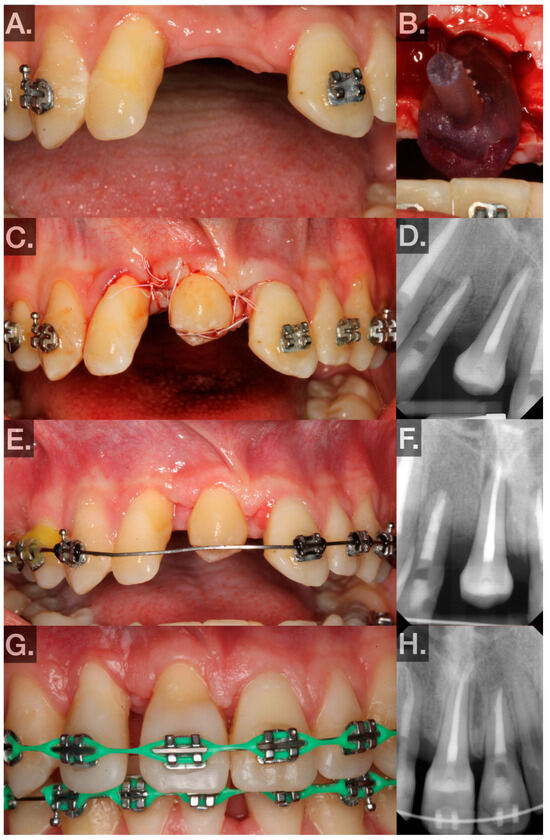

- No. 24 (FDIn no. 31) → no. 7 (FDIn no. 12) (Figure 3A–H; 9/2023):- ▪

- First, 1.5 carpules of Septocaine® (articaine hydrochloride 4% and epinephrine 1:100,000; Septodont, Saint-Maur-des-Fossés, France) were used to anesthetize the donor tooth and recipient sites through local infiltration. Midcrestal and sulcular incisions were made and a full-thickness flap was elevated around tooth no. 7 (FDIn no. 12). The tooth was then extracted using elevators and forceps. The extraction socket was widened using an implant motor (Implant 900, Denstply Sirona, Charlotte, NC, USA) and implant drills (Bone Level Tapered Drills, Straumann AG, Basel, Switzerland). The osteotomy was prepared to be slightly larger than the measurements made on the CBCT. After the recipient site was prepared, the replica of the donor tooth was tried in. Passive fit and subocclusal positioning were verified. Luxation forces were made with forceps on tooth no. 24 (FDIn no. 31) using slow rotational movements only. Special care was taken to ensure the beaks of the forceps did not sit apical to the CEJ. Tooth no. 24 (FDIn no. 31) was extracted atraumatically and immediately placed into the artificially created socket after a photograph was taken to demonstrate the intact PDL (Figure 3B). The extra-alveolar time was less than 30 s. The tooth was fixated in the recipient site with 4–0 polytetrafluoroethylene (Cytosurg® PTFE, Salvin, Charlotte, NC, USA) sutures via a Laurell–Gottlow suture technique [22]. Because of the small occlusal surface area, composite resin (Filtek™ Supreme Flowable Restorative, 3M™, Saint Paul, MN, USA) was bonded to the tooth to hold the suture in place. Simple interrupted sutures were also used to approximate the tissue interproximally (Figure 3C). A periapical radiograph was then taken as a baseline for evaluating healing (Figure 3D).

- Postoperative visits at 1, 3, and 6 weeks and 3, 6, and 12 months were planned.- ▪

- At 1 week, sutures were removed, and the patient was instructed to use a soft surgical toothbrush (Rx Ultra Suave, PHB Toothbrushes, Osseo, WI, USA) dipped in chlorohexidine twice daily to clean the clinical crown of the transplant for 2 weeks.

- ▪

- At week 3, bleeding on probing (BOP), probing depth (PD), and mobility were measured at 6 sites to evaluate periodontal healing (Figure 3E). The patient was instructed to resume normal brushing and to use the tooth in normal function.

- At week 6, BOP, PD, and mobility were measured at 6 sites to evaluate periodontal healing.

- Between weeks 6 and 8, the transplanted teeth were restored with composite resin (Filtek™ Supreme Ultra Universal Restorative, 3M™, Saint Paul, MN, USA) and orthodontically loaded with low-force 0.016 NiTi wires. Special care was taken at this point to avoid intrusive orthodontic forces.